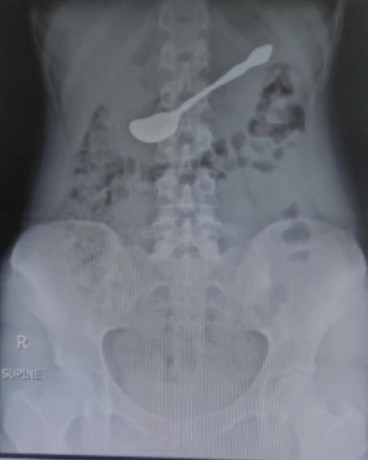

शल्यक्रियाबिनै निकालियो पेटमा अड्किएको चम्चा

४५ मिनेट लामो जटिल इन्डोस्कोपी प्रक्रियापछि अड्किएको चम्चा निकालियो

काठमाडौं थापाथलीस्थित नर्भिक अस्पतालका चिकित्सकले शल्यक्रिया नगरी आमाशयमा अड्किएको चम्चा निकालेका छन् । नर्भिक अस्पतालका पाचन रोग विशेषज्ञ डा.सन्दीपराज कुँवर नेतृत्वको टिमले आइतवार काठमाडौंकी १७ वर्षीया किशोरीको पेटमा अड्किएको चम्चा निकालेको हो ।